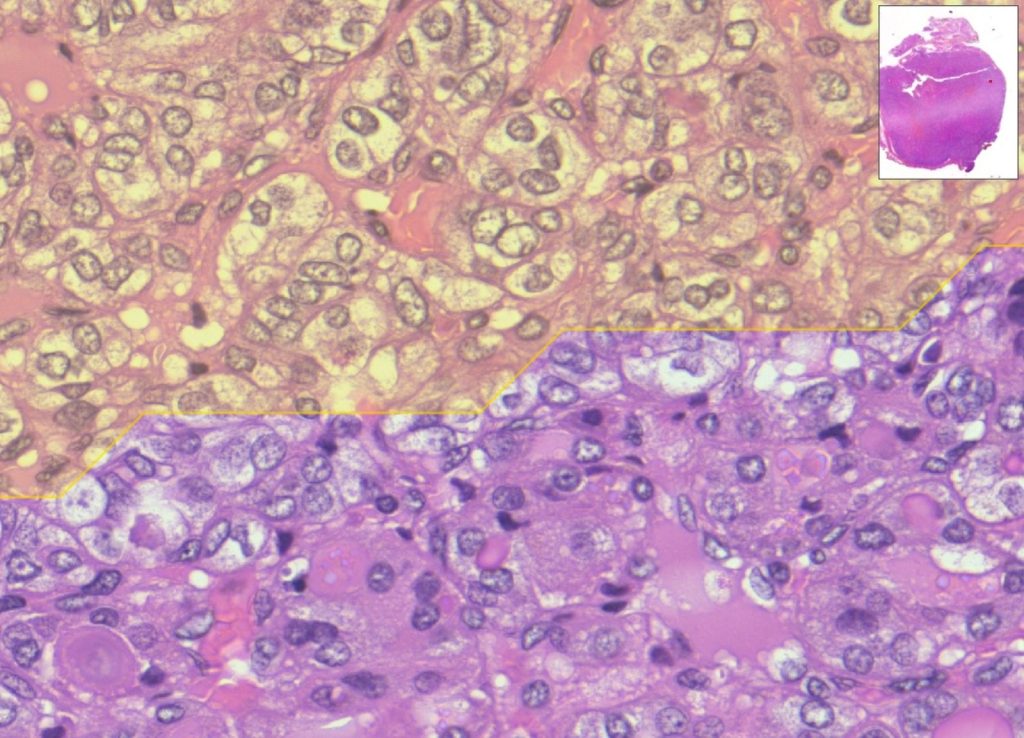

Si tratta di un algoritmo di digital pathology in grado di analizzare immagini istologiche ad altissima risoluzione in grado di fornire un aiuto significativo ai medici nella diagnosi di tumori. Il sistema utilizza reti neurali profonde (strumenti di deep learning, dunque basate sull’Intelligenza Artificiale) addestrate su migliaia di campioni digitalizzati con scanner molto potenti (l’immagine ricavata dai vetrini istologici su cui si trovano le cellule da analizzare) per identificare automaticamente aree, cellule, marcatori sospetti, spesso difficili da rilevare da parte dell’occhio umano.

L’Intelligenza Artificiale analizza l’immagine del campione e punta letteralmente il proprio sguardo in modo rapido sulle aree che meritano l’attenzione dei medici, velocizzando in tal modo la diagnosi e rendendola più efficace. Più nello specifico, il sistema sviluppato nella ricerca mette in campo un “doppio occhio”, due reti neurali che lavorano in sequenza: un primo “occhio digitale” coglie i dettagli delle cellule, un secondo “occhio” considera la visione d’insieme dell’immagine. Integrando le due letture, MiThyCA indica le aree che è opportuno analizzare per prime.

Negli studi condotti su casi di carcinoma tiroideo, l’algoritmo ha raggiunto un’accuratezza diagnostica paragonabile a quella di un team esperto, fornendo un secondo parere, accanto a quello umano – sempre presente durante la diagnosi – oggettivo e riproducibile. In futuro, il vetrino del proprio esame istologico non dovrà più viaggiare tra laboratori o specialisti, che necessitino del campione fisico per eseguire la diagnosi: basterà un’immagine digitale, che potrà essere analizzata in modo efficace dall’AI e dal medico per individuare rapidamente la natura di una lesione o la risposta a una terapia. Questo si traduce in tempi di attesa ridotti, minore incertezza per i pazienti, e nella possibilità di avviare prima percorsi di cura personalizzati.